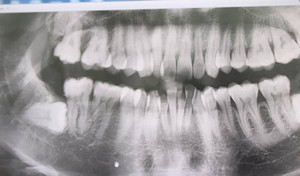

Những biến chứng khủng khiếp do răng khôn mọc lệch

Các chuyên gia cho biết, răng khôn khi mọc lệch có thể gây nhiều biến chứng nguy hiểm tới tính mạng.

BS buộc phải đình chỉ thai để điều trị kháng sinh do răng khôn áp xe nặng, tạo ổ mủ, thủng má.